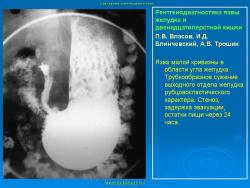

Пищеварительная система. Рентгенодиагностика язвы желудка и 12-ти перстной кишки. +

Рентгенодиагностика язвы желудка и 12-ти перстной кишки.

Данная статья помещена не только с познавательной целью, но и в дискуссионном плане.